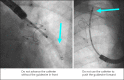

Endobronchial coils are an additional treatment option for lung volume reduction in patients with severe emphysema. Patient selection should be focused on patients with severe emphysema on optimal medical therapy and with evidence of severe hyperinflation. The technique is suitable in a broad range of patients with emphysema; however, patients with paraseptal emphysema, large focal (giant) bullae, significant co-morbidity and airway-predominant disease should be avoided. Treatment involves placing between 10 and 14 coils by bronchoscopy in the selected treatment lobe, with 2 lobes being treated sequentially. Lobe selection for treatment should be based on quantitative computed tomography, and the lobes with the greatest destruction should be targeted (excluding the right middle lobe). The treatment results in an improvement in pulmonary function, exercise performance and quality of life, particularly in patients with severe hyperinflation (residual volume > 200% predicted) and upper-lobe heterogeneous emphysema, but will also be of benefit in lower-lobe predominant and homogeneous emphysema. Finally, it has an acceptable safety profile, although special attention has to be paid to coil-associated opacity which is an inflammatory response that occurs in some patients treated with endobronchial coils.